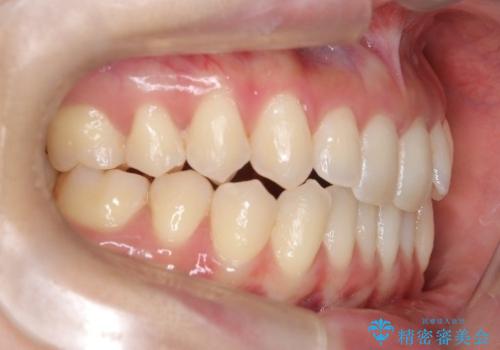

再矯正 前歯のガタツキをマウスピース矯正で治療したい

- 前に矯正治療をしたが、後戻りしてガタツキが出てきたので、治したいとのことで来院されました。

ワイヤー治療とマウスピース矯正、2通りの治療を提案させていただき、マウスピース矯正治療を希望されましたので、インビザラインによる治療を開始しました。

- 20代女性

- 11ヶ月

- 10-30回

- 55万円費用は治療当時の料金となります